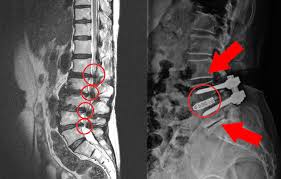

허리협착증을 진단하기 위해서는 전문 의료진의 평가가 필요합니다. 일반적으로 X-ray, MRI와 같은 영상검사를 통해 척추의 상태를 확인하게 됩니다. 이러한 검사는 척추관의 협착 정도를 평가하고, 다른 척추 질환과의 차별화를 가능하게 합니다. 또한, 환자의 증상에 대한 자세한 청취와 신경학적 검사를 통해 진단이 이루어집니다. 따라서 의사와의 상담을 통해 알맞은 진단을 받는 것이 중요합니다.

- X-ray 검사

- MRI 검사

허리협착증의 치료 방법은 여러 가지가 있습니다. 초기 단계에서는 비수술적 치료가 주로 시행되며, 물리치료, 약물치료, 주사치료 등이 포함됩니다. 이러한 치료는 통증을 경감시키고, 근육의 긴장을 완화하여 재활을 돕는 역할을 합니다. 만약 이러한 비수술적 치료로 효과를 보지 못하거나 증상이 심각한 경우에는 수술적 치료가 필요할 수 있습니다. 수술적 방법으로는 신경을 압박하는 요소를 제거하여 척추관을 넓히는 방법이 있습니다.